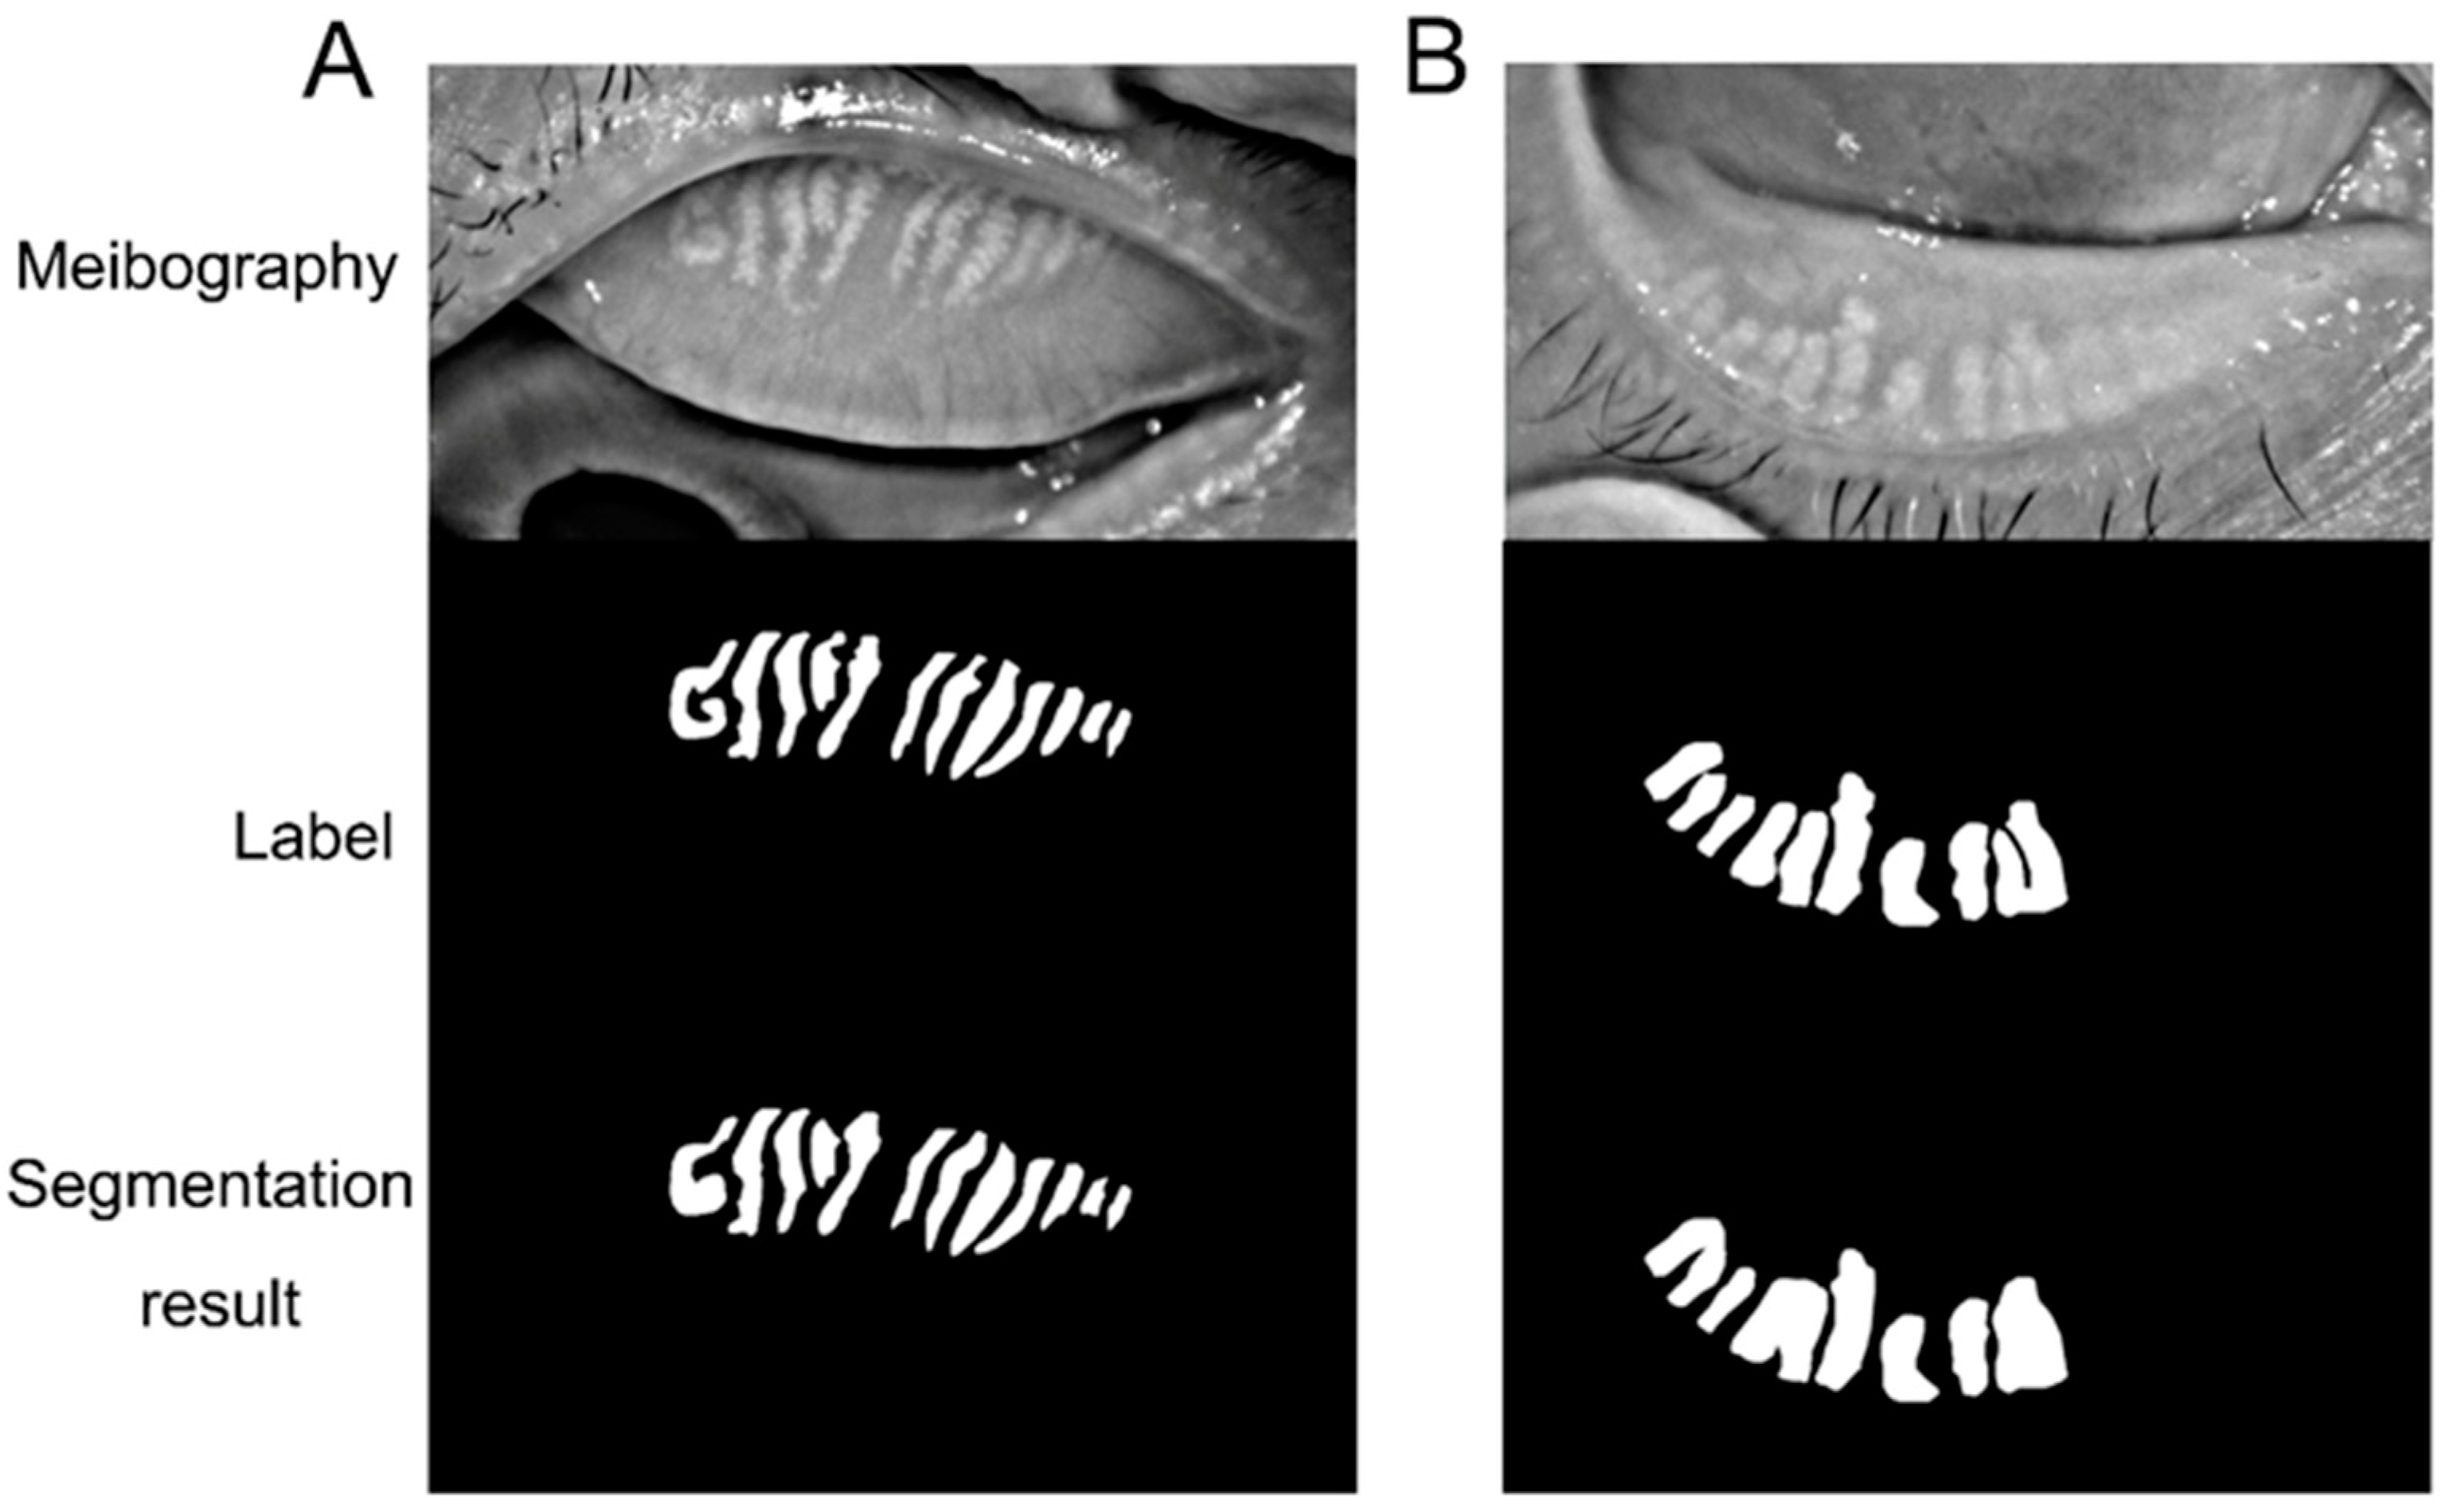

The present study further included infrared meibography and annotated the contour of each meibomian gland and tarsus area. Then we trained a convolutional neural network-based deep learning model to automatically identify the meibomian gland and tarsus area and compare the results with the manual label. The model could be potentially applied to assess the meibomian gland that facilitates dry eye evaluation in various scenarios.

Previous research achieved good performance by applying deep learning models to segment meibomian glands automatically. When annotating the whole region of the meibomian gland as the ground truth, Lin et al.’s study achieved an accuracy of 95.4% on meibomian gland atrophy segmentation [